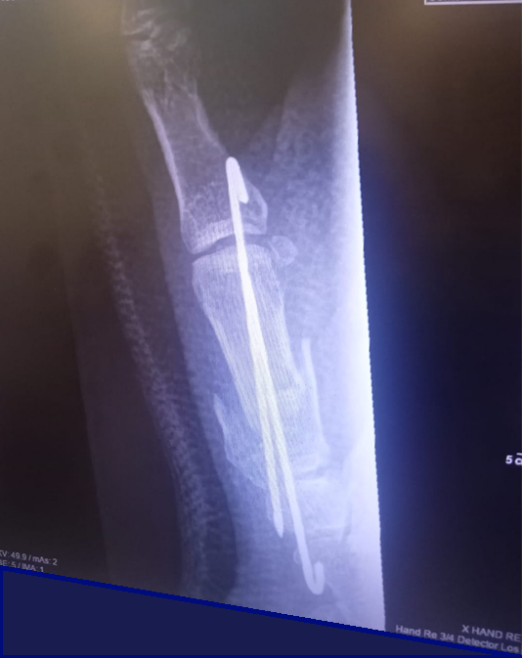

In het ziekenhuis werd direct duidelijk dat de cirkelzaag veel schade had aangericht. Pezen van de duim waren doorgesneden, spieren waren gescheurd en twee zenuwen beschadigd. Ook het bot aan de onderkant van zijn duim was gebroken. Dr. Dolmans, Dr. Louwerens en Dr. Theunissen hechtten tijdens een spoedoperatie alle beschadigde delen en maakten het gebroken bot weer vast. Er volgden 6 weken in het gips, waarbij Benny alleen zijn vingers kon bewegen.

Röntgenfoto na operatie met stabilisatie van het basis duimbot Gipsspalk na operatie